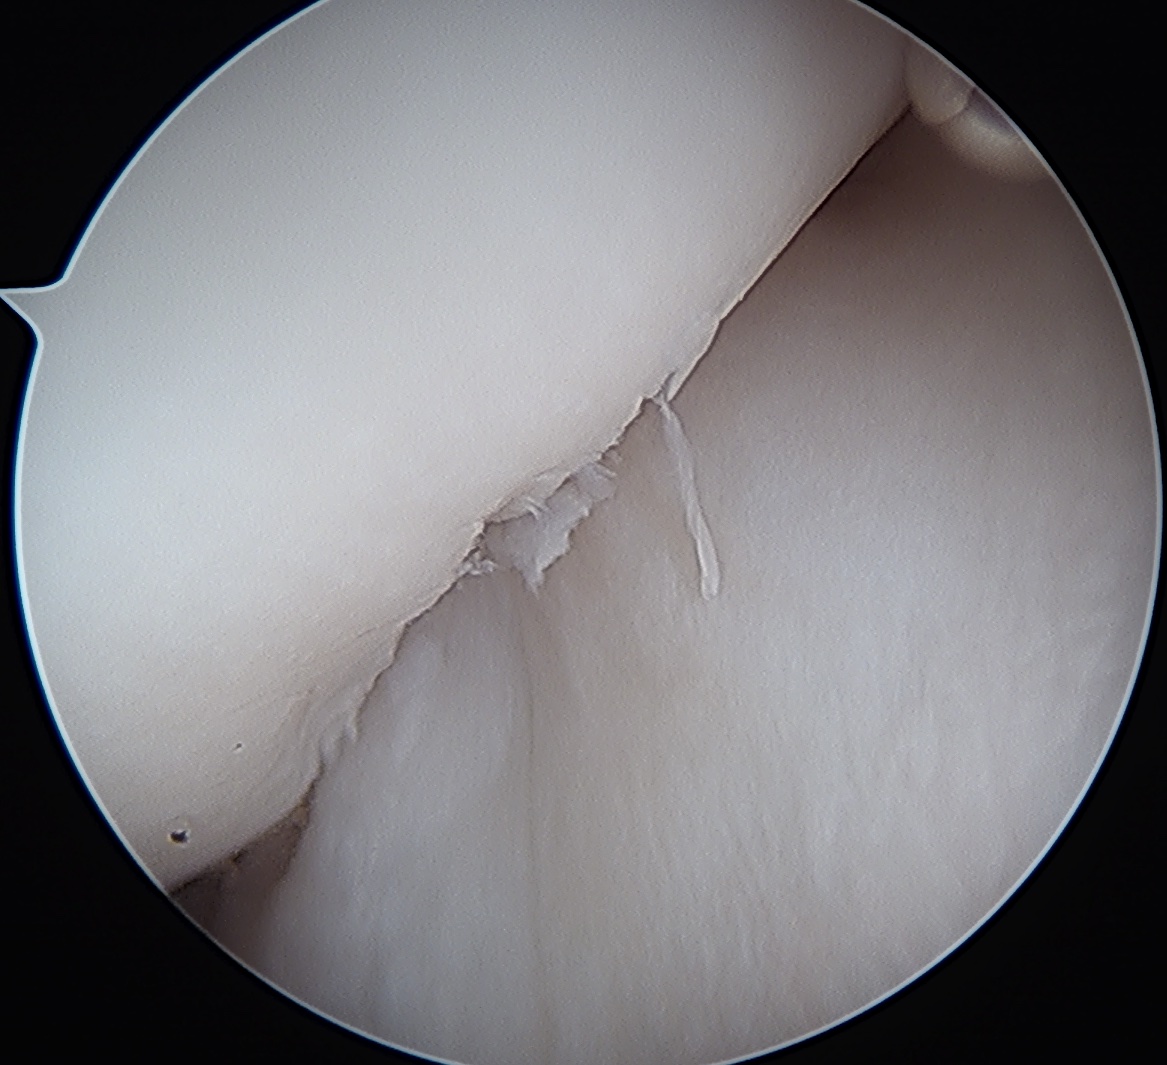

Engaging / Large Hill Sachs lesion

Filling Hill Sachs defect with infraspinatus / posterior capsule

- debride base of Hill Sachs to bleeding bone